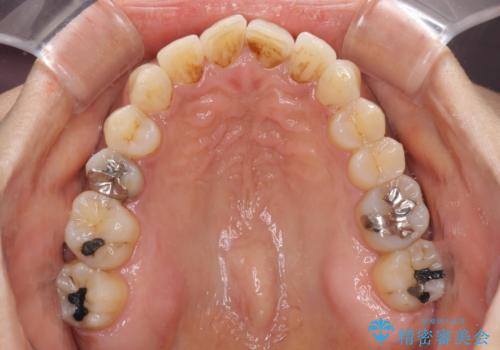

- 40代女性

- インビザライン

- 上下前歯のデコボコ改善をインビザラインにて行いたいとのことで来院された患者様です。

インビザラインをご希望のことで、IPR(歯と歯の間を削る)などによりスペースを獲得して、排列していくこととしました。

骨格的に上下顎が左右にずれていたため、正中位置は現状を維持したまま歯列不正を解消していくことになります。

なかなか装着時間が守れず、後戻りを繰り返しながら治療を進めたため、インビザライン治療期間期限ギリギリの5年弱の期間を要しました。